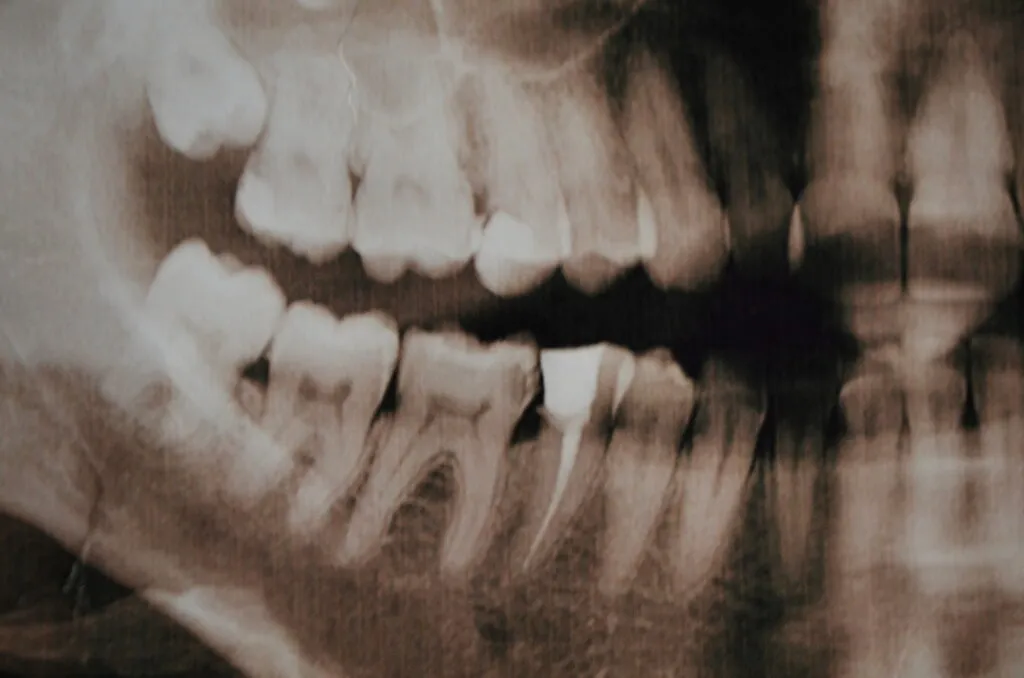

How is a Fractured Cusp Diagnosed?

Dentists have different methods to diagnose cracked teeth and fractures early. These methods include:

- Radiograph — Uses X-rays and bitewing imaging to determine overall tooth status.